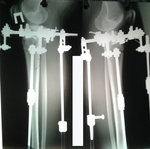

перед крутками.

Вложения